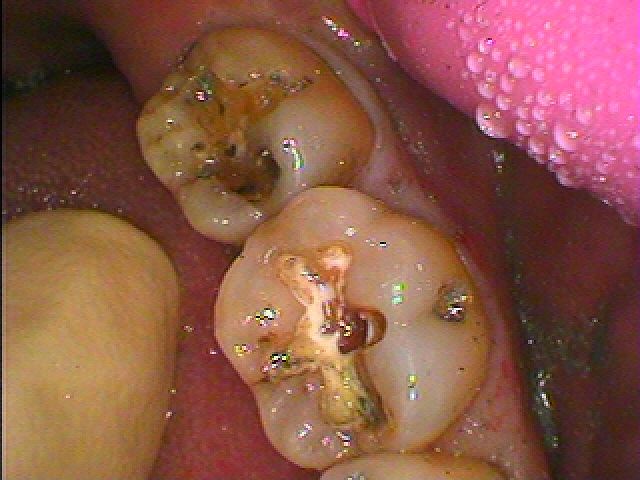

問題のアマルガムが入っている歯になります

中は悪くなっています

虫歯が出てきました

かなり深部にまで年月とともに進行していました